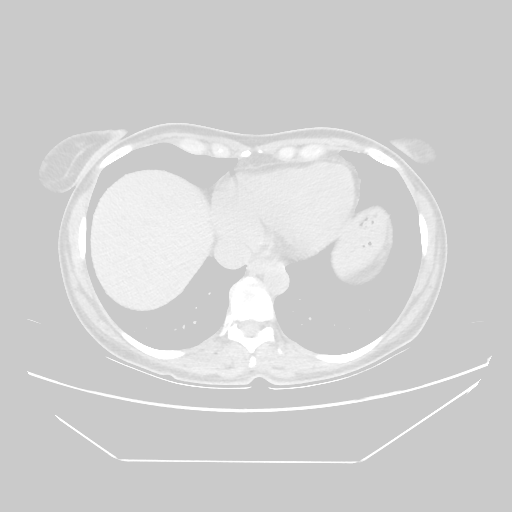

Slice 70 Targeting Evaluation

Slice: Slice_70

Conversion: NATIVE β†’ VENOUS

Image Grid

4Γ—3 grid: Rows show different image types (Original NATIVE, Reconstructed NATIVE, Original VENOUS, Generated VENOUS), Columns show windowing techniques (No Window, Lung Window, Mediastinum Window)

Lung window (WL -600, WW 1500 β†’ Low βˆ’1350, High +150)